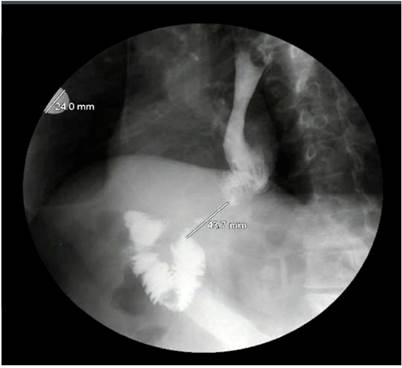

As a result of these findings, an x-ray of the digestive tract was performed (Figure 3), in which ileum stenosis of 43 mm, distal to anastomosis, was observed, suggesting the possibility of tumor relapse. Therefore, a computed tomography (CT) scan of the abdomen was performed, in which post-surgical changes of the total gastrectomy, Roux Y reconstruction, and thickening of the intestinal wall at sites of esophagojejunal and jejuno-jejunal anastomosis, with no signs of intestinal obstruction, were observed.